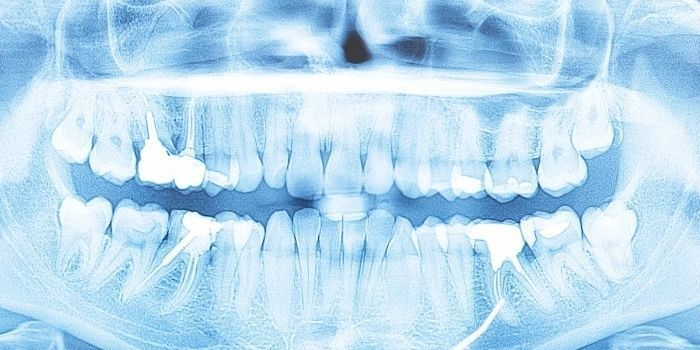

Digital Imaging

Digital imaging, or digital radiography, is a valuable diagnostic tool frequently used in dentistry, as well as other disciplines. It is an innovative technique that uses a computer to efficiently manipulate and store x-ray images. This technology provides immediate results and is readily available for sharing and discussion with patients and other medical or dental professionals.